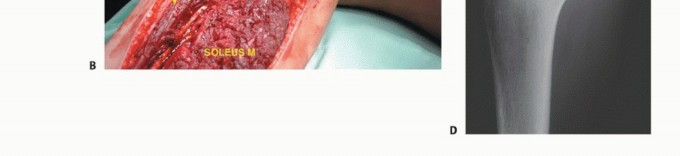

استئصال جسم الشظية (Intercalary Resection)

- الإشارة: تُعالج أورام جسم الشظية، سواء كانت حميدة أو خبيثة، عادةً باستئصال الجزء المصاب من جسم الشظية. لا يُعد الكشط ممكنًا أو فعالًا هنا بسبب صغر قطر جسم الشظية.

- الإجراء: يتم إزالة الجزء المصاب من العظم. فقدان هذا الجزء لا يؤثر عادةً على استقرار مفصلي الركبة والكاحل أو الوظيفة العامة للطرف السفلي.

- الأورام الخبيثة: تتطلب إزالة شاملة لغلاف العضلات المحيطة.